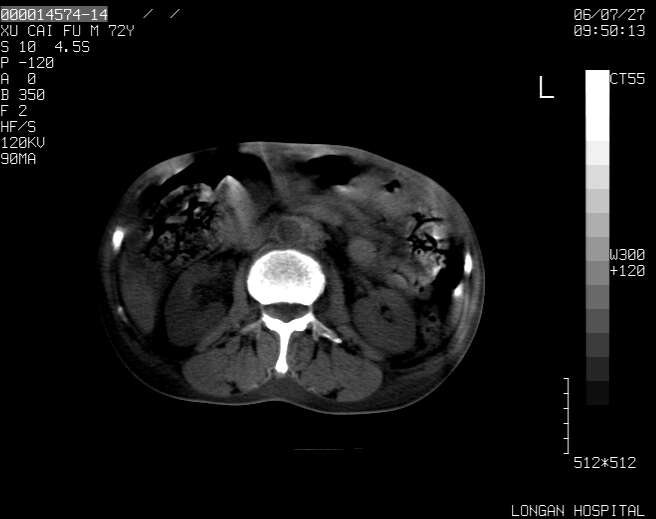

以下是引用winter在2006-7-30 20:14:00的发言:[br]1、考虑胆囊癌伴胆道侵犯并高位胆道梗阻、肝内多发转移、腹膜后淋巴结转移。[br]2、右肾轻度积水。[br]3、老人家72岁了胰腺头体尾部均较饱满,不过未见密度异常及其他异常征象。[br]4、腹水。

以下是引用jiajie在2006-7-31 7:10:00的发言:[br]考虑肝转移瘤,腹膜后淋巴结增大。[br]胃癌不能除外,建议胃镜检查。